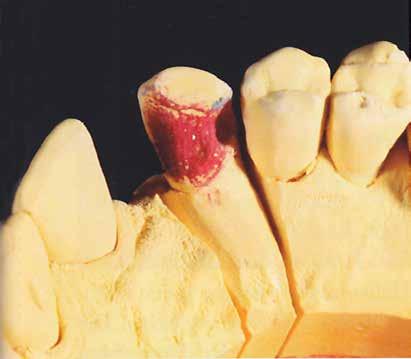

A laboratóriumban szekciós minta készült, blokk-stiftekkel (1. kép) , amelynek készítése során nagy figyelmet szenteltünk az ínymaszk (Majesthetik- Gingiimplant picodent) és a felfekvő lengőtag területének (2–6. képek)

A minta beolvasása után számítógéppel terveztük meg a híd vázát (7. kép). 0,06 mm-es cementrést terveztünk a teljes karfelület alá, 1 mmre végződve a preparáció szélétől (8–11. képek)